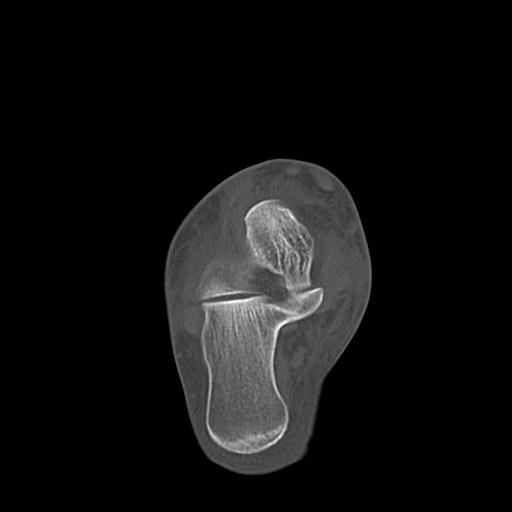

102766 1/5 1/12 左手関節 4R 28歳男性 左橈骨遠位端